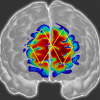

Researchers in the UK and USA have used functional near infrared spectroscopy to discover that the cocoa flavanols found in chocolate improve brain oxygenation and cognition in healthy adults.

Functional near infrared spectroscopy has been used to identify tinnitus in patients.

fNIRS could help diagnose pain in non-communicative patients.